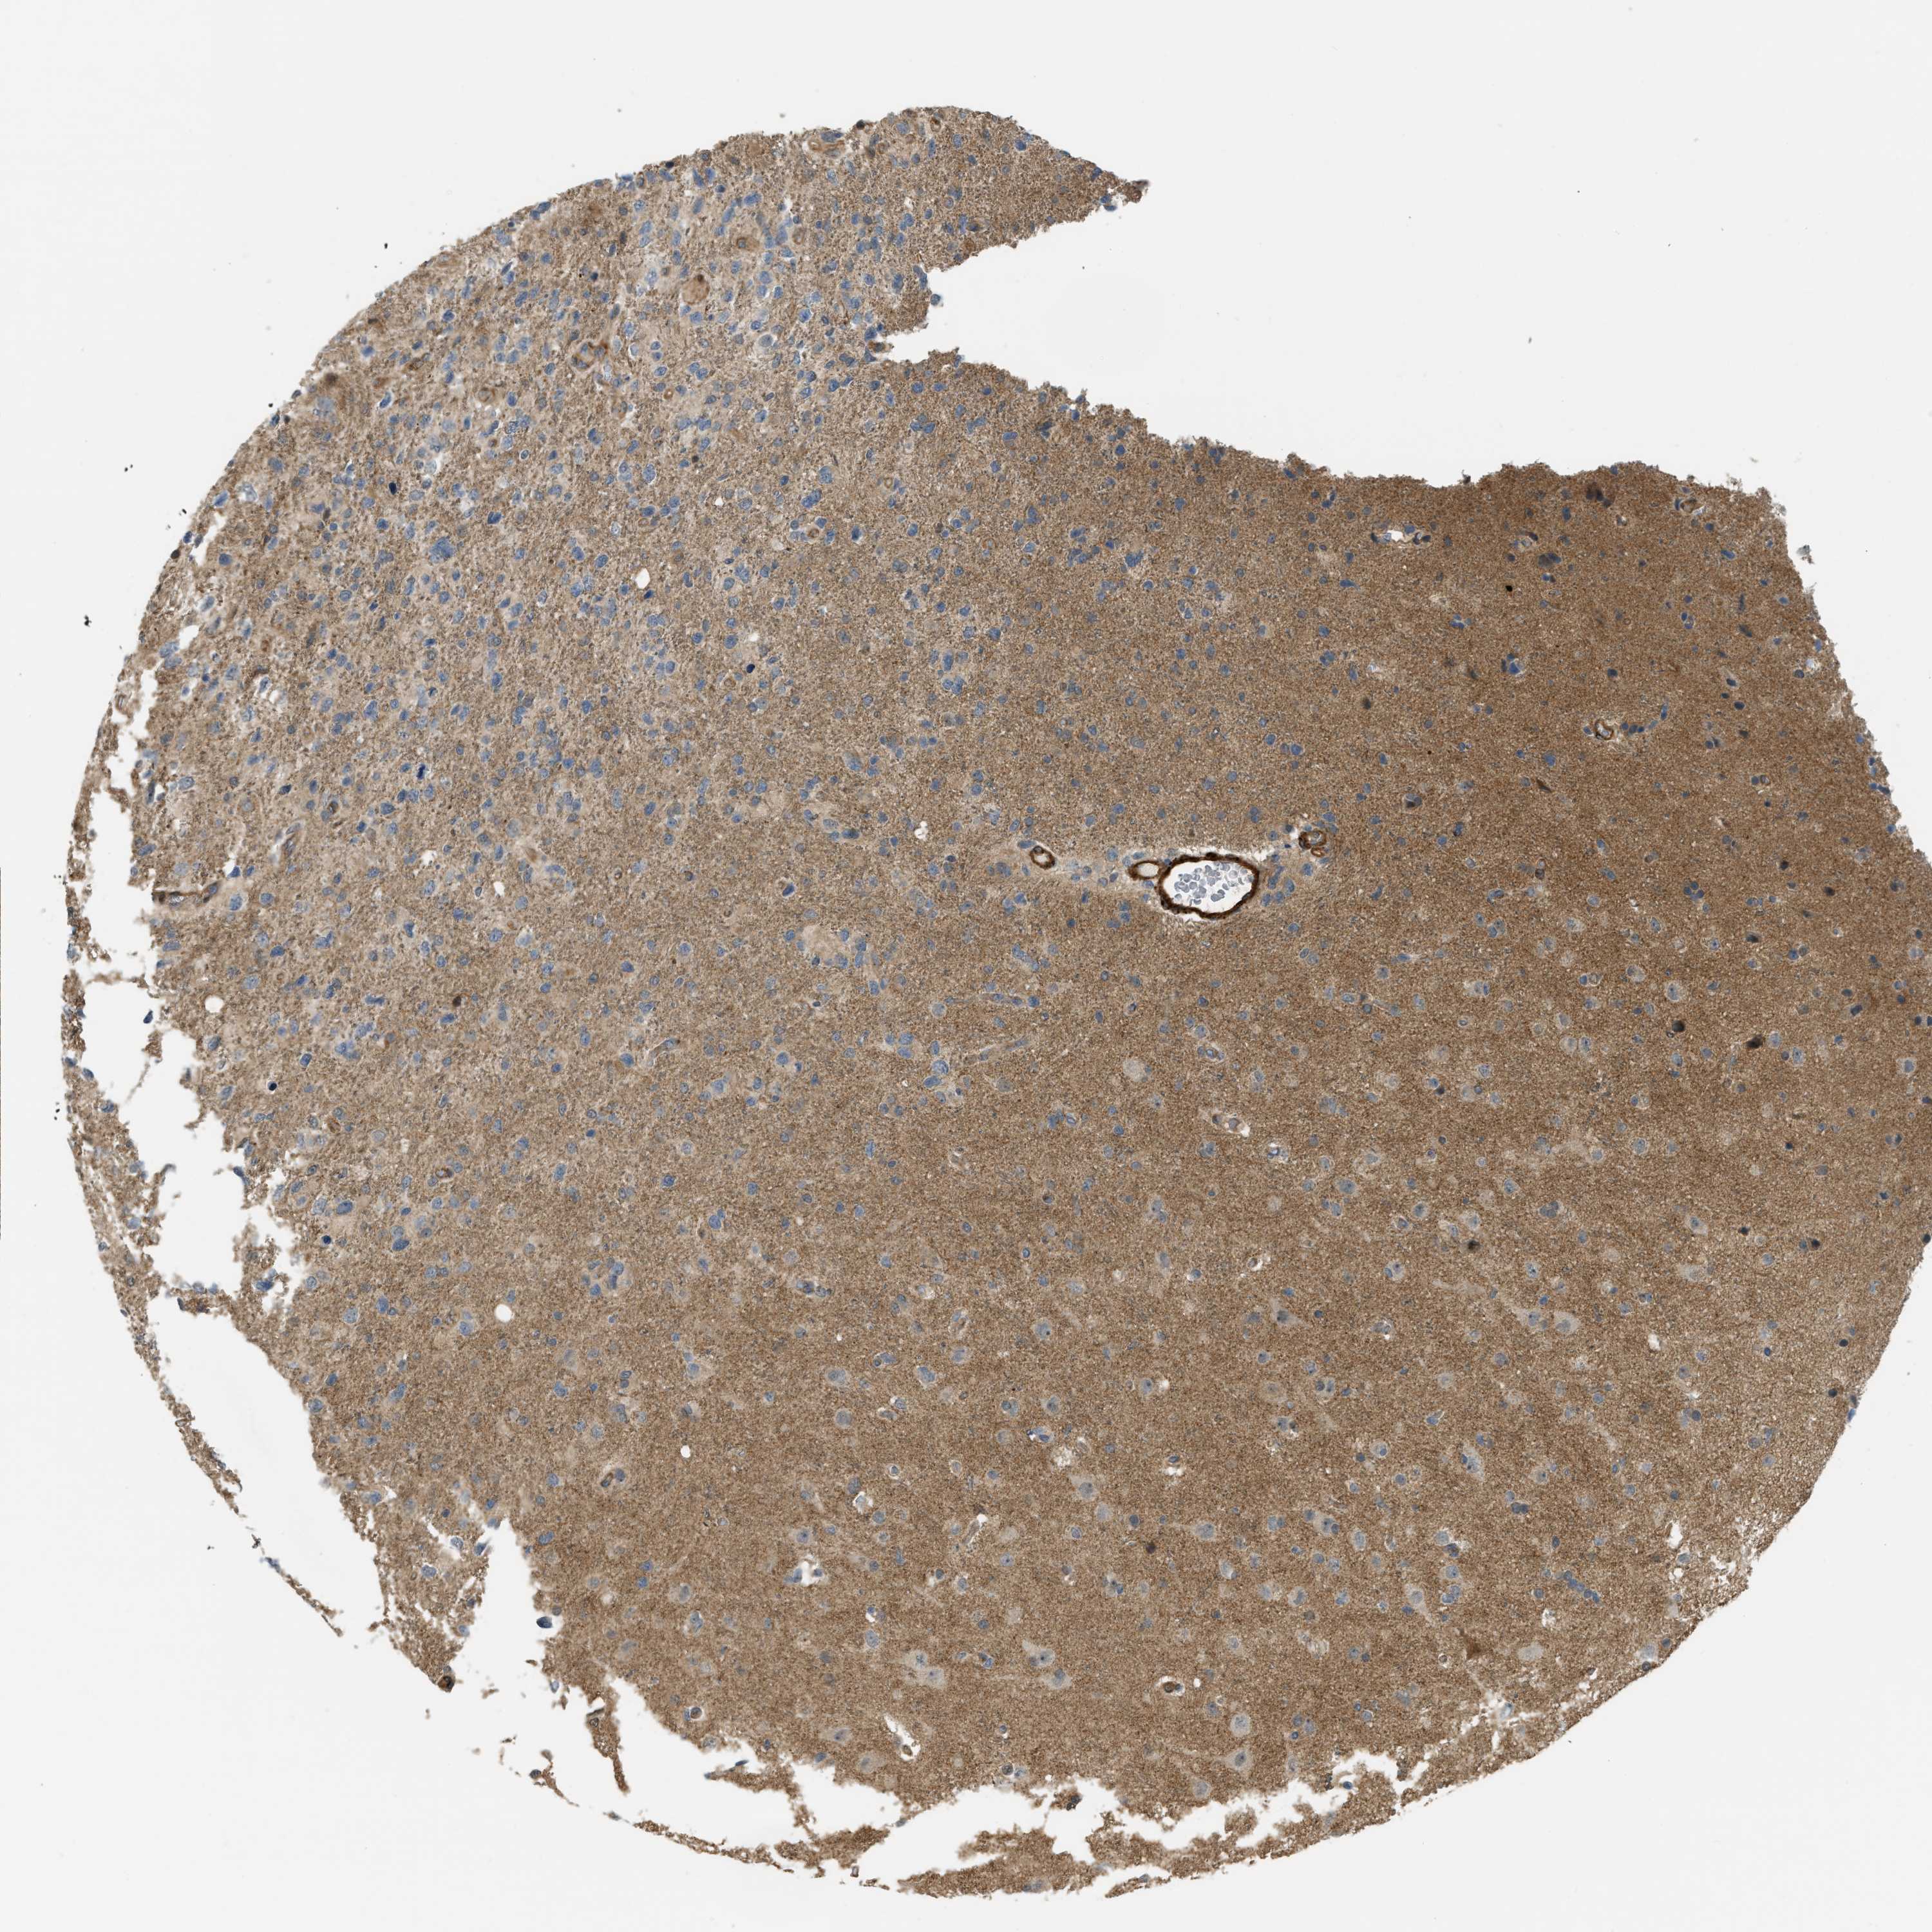

GLIOMA - Protein expressioni

A mouse-over function shows sample information and annotation data. Click on an image to view it in a full screen mode. Samples can be filtered based on level of antibody staining by selecting one or several of the following categories: high, medium, low and not detected. The assay and annotation is described here.

Note that samples used for immunohistochemistry by the Human Protein Atlas do not correspond to samples in the TCGA dataset.

Antibody stainingi

Antibody staining in the annotated cell types in the current human tissue is reported as not detected, low, medium, or high, based on conventional immunohistochemistry profiling in selected tissues. This score is based on the combination of the staining intensity and fraction of stained cells.

Each image is clickable and will lead to virtual microscopy that enables deeper exploration of all samples and also displays staining intensity scores, fraction scores and subcellular localization as well as patient and tissue information for each sample.

Antibody HPA018135

Staining

High

Medium

Low

Not detected

Intensity

Strong

Moderate

Weak

Negative

Quantity

>75%

75%-25%

<25%

None

Location

Nuclear

Cytoplasmic/membranous

Cytoplasmic/membranous,nuclear

Glioma, malignant, High grade

Glioma, malignant, Low grade